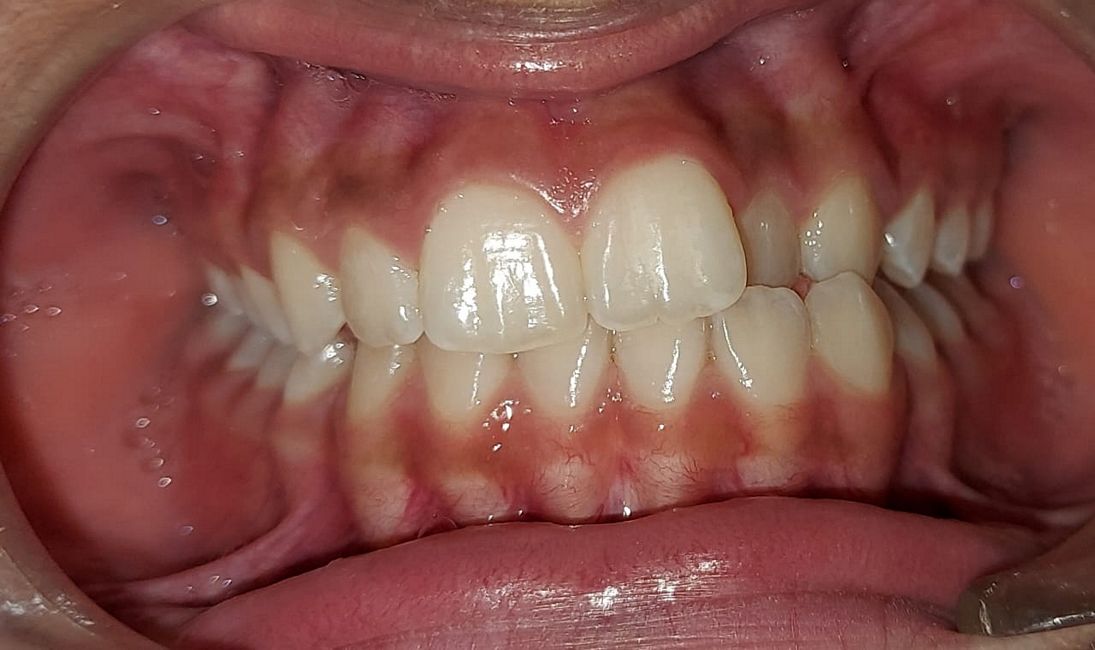

Case No: 22

Malocclusion Type: Class I Malocclusion.

Mechanics: MBT Mechanics.

Treatment: Class I Malocclusion with crowding in upper and lower anteriors treated by Non-extraction (permanent teeth)method.